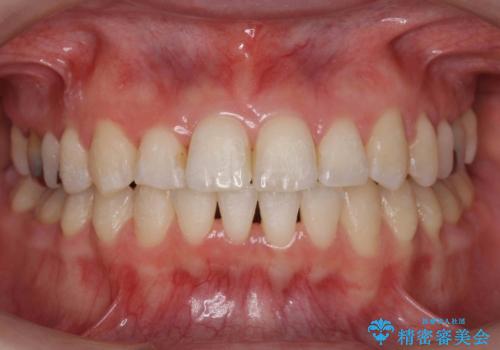

矯正歯科治療 → 叢生(でこぼこ・八重歯)

インビザラインによるガタつきの矯正治療 シンプル・短期間

前歯がガタガタ・噛み切りにくい インビザラインによる歯を抜かない矯正

Invisalign インビザラインによる軽度なガタつきの改善